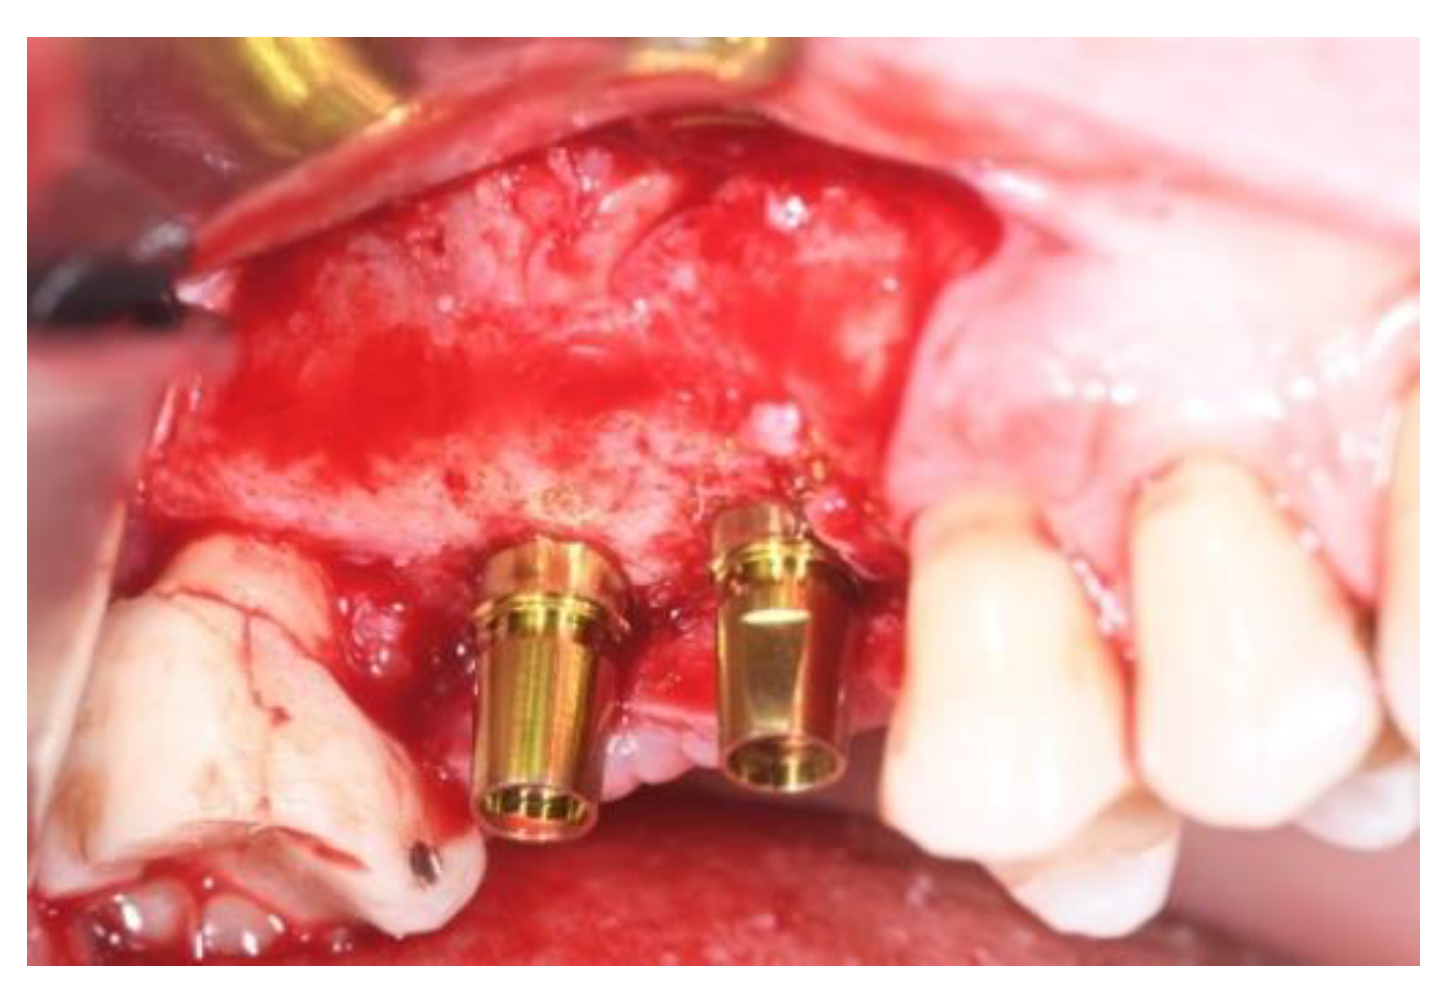

2.1. Surgical Procedures